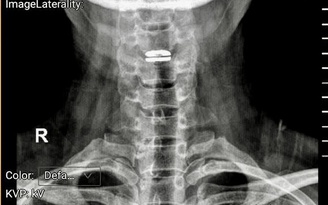

- Ảnh 1.

Khối u ổ bụng được phát hiện khi đã phát triển lớn ở bệnh nhi

ẢNH: Đ.X

Theo các bác sĩ, điểm chung đáng lo ngại là 3 trường hợp đều được phát hiện khi khối u đã phát triển lớn, gây chèn ép các cơ quan trong ổ bụng, khiến việc phẫu thuật trở nên phức tạp, đồng thời làm tăng nguy cơ phải điều trị phối hợp nhiều phương pháp sau mổ.